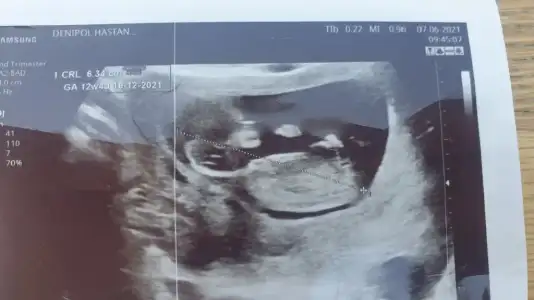

Net değil USG başka USG varsa paylaşın

Yenisi ekledimNet değil USG başka USG varsa paylaşınkız sanki emin olamadım

Kız görünüyorYenisi ekledim![]()